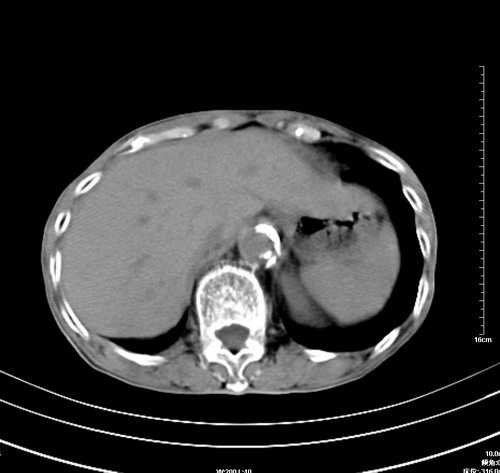

病人,女,79岁,主要因腹疼二月入院,彩超,肝,胆,脾,未见异常,胸透上消化道造影未见异常,化验白细胞增高,内科医生让做胸部ct检查,因为熟人多做了腹部(外科会诊考虑胆囊炎).现ct片如下请假各位战友.

1 气管旁、隆突下淋巴结明显肿大,肝左叶外侧段低密影,都考虑转移。

2 肝右后叶下段明显增大,片状低密影,但因各种伪影显示不佳,不排除病变。

后中纵隔团块影,伴气管、食道受压移位,首先考虑转移瘤,肝s5段低密度灶。建议增强检查,另外其结肠是否有问题请提供,右肺部分肺叶局限含气增多,考虑局限肺气肿。

后中纵隔团块影,伴气管、食道受压移位,首先考虑转移瘤,肝表现同11773。